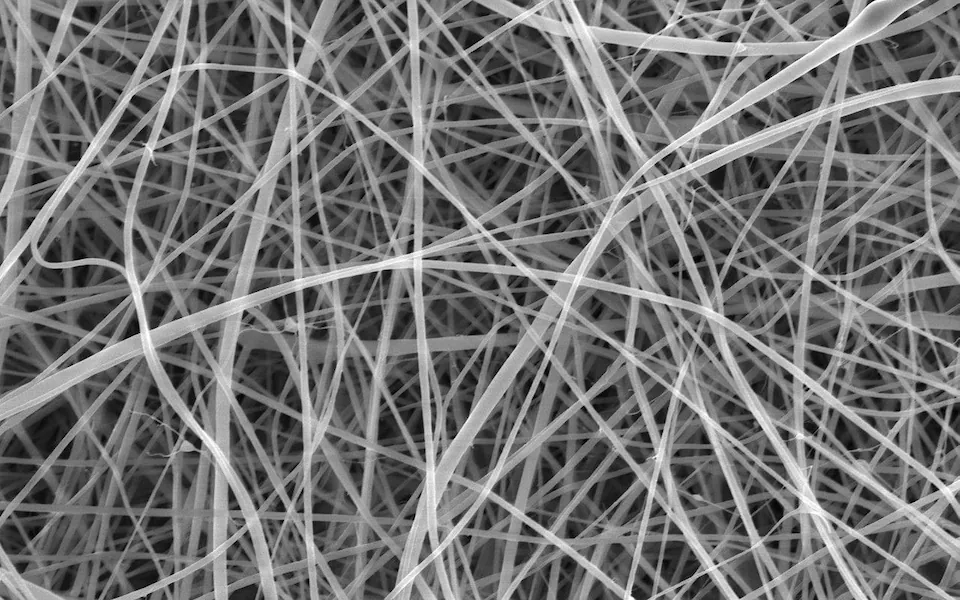

Nem bírja tovább kitermelni kötszerei árát a Mediq Direkt Kft., ezért úgy döntött, elhagyja a magyar piacot. Nehéz lesz pótolni egy olyan céget, amelynek munkatársai házhoz is mentek, ha

Kötszer-ügy: még egy-két ilyen intézkedés és már ellátás sem lesz

Havonta 20 darabról 15-re csökkentenék a felírható kötszerek számát egy jogszabálytervezet szerint. Rásky László, az Orvostechnikai Szövetség főtitkára szerint a betegek jelentősen drágábban

Állapottól függően akár másfél-kétszeresére is nőhet a betegteher a dráguló kötszerek miatt – mondta az InfoRádióban az Orvostechnikai Szövetség főtitkára. Rásky László figyelmeztetett: a rendszeres kötözésre szoruló betegek költségei jelentős mértékben megemelkedhetnek, ha a tervezetből jogszabály lesz. Árváltozás jön az injekcióknál és a pelenkáknál is.